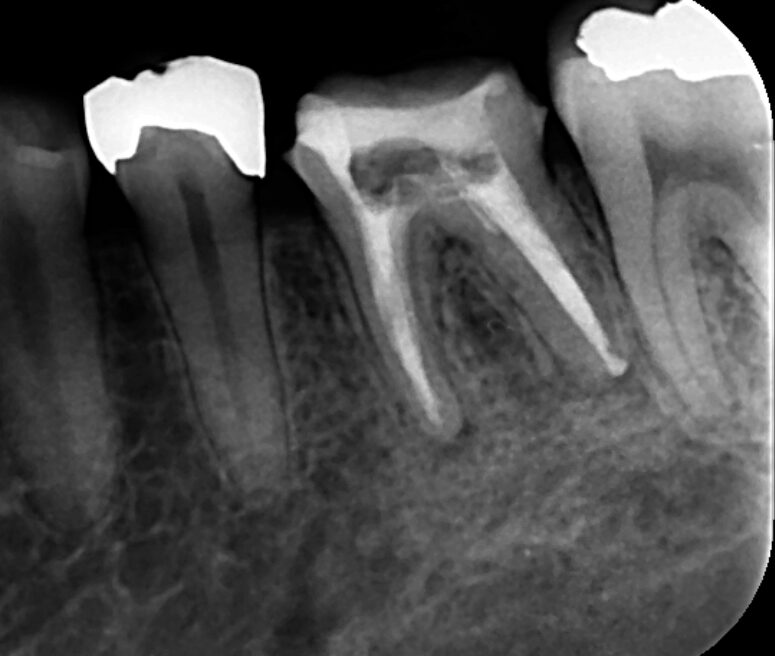

精密根管治療を行いました。画像は根管充填時のレントゲン写真です。